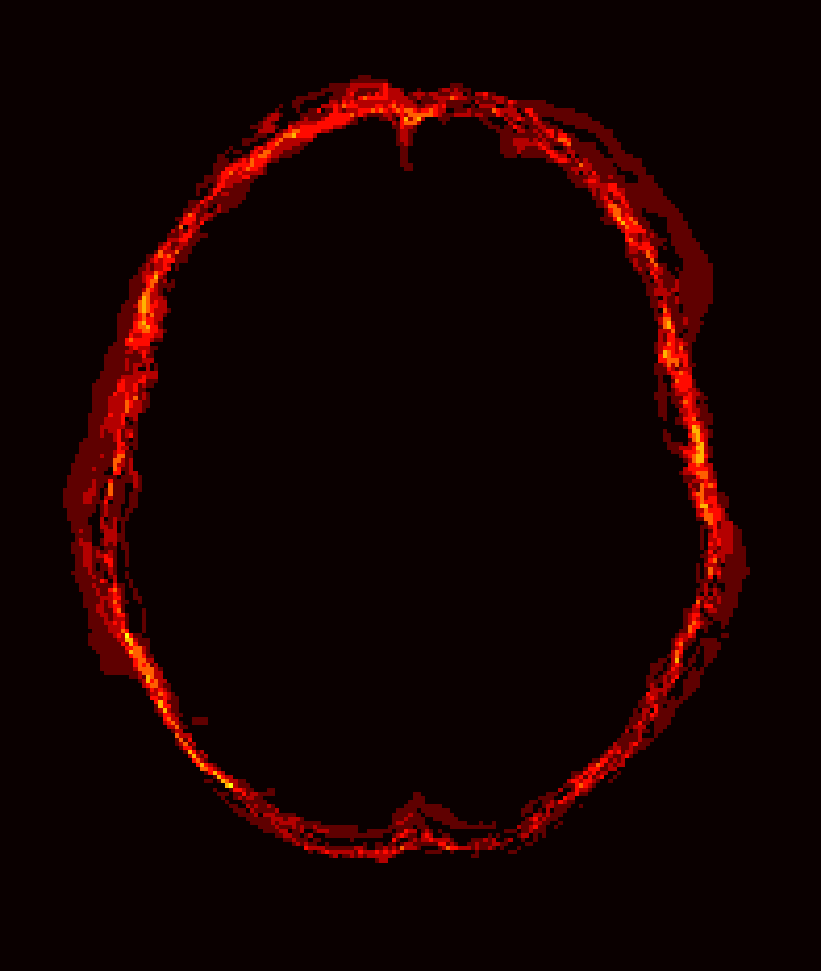

Fig. 1 shows example images from each dataset to illustrate image variability. IBSR and LPBA40 contain images from normal subjects and include large portions of the neck; BRATS has very low out-of-plane resolution; and the TBI dataset contains large pathologies and abnormal skulls.

Refer to caption

Figure 1: Illustration of image appearance variability on a selection of images from each (evaluation) database. From top to bottom: IBSR, LPBA40, BRATS and TBI.